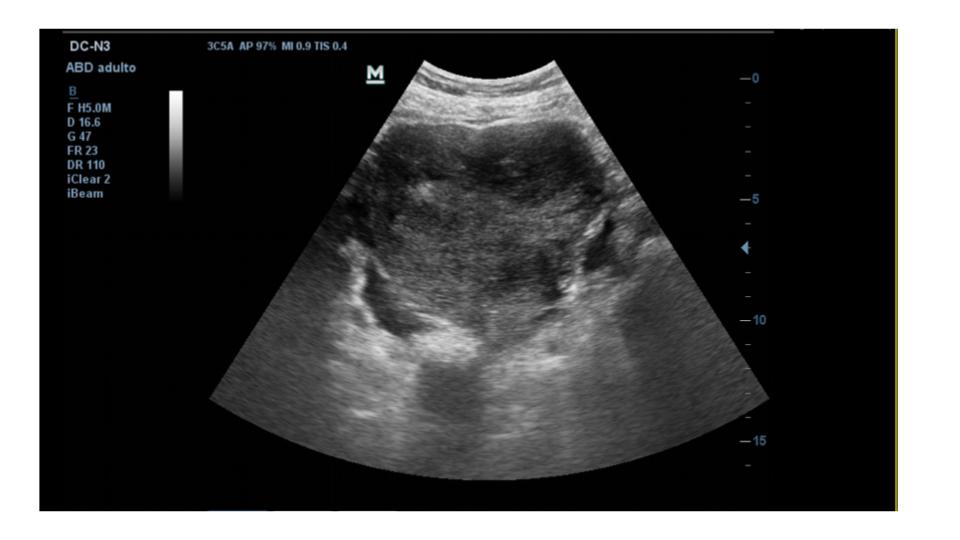

Se realiza ecografía clínica abdominal en el mismo acto para confirmar presencia de líquido y tratar de identificar la ocupación en flanco derecho.

La ecografía confirma la presencia de moderada cantidad de líquido libre abdominal y de una imagen de unos 10 cm de diámetro mayor, anecogénica, tabicada, que parece depender de ovario derecho.